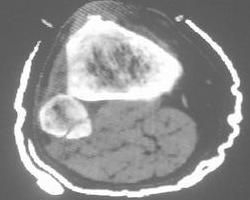

X線表現

長春新鹼在長骨髓腔內有浸潤性的破壞灶,呈斑點狀或大範圍的片狀溶骨性改變最為突出,病變範圍和邊緣模糊不清,皮質非常不規則地有缺損和破壞。骨膜反應早而多。反應性新骨形成產生Codman三角,或者骨膜反應呈同心性、成層狀排列似洋蔥皮樣改變,前者比後者多見。在長骨雖然主要見於骨幹,起源於乾骺端者並不少見。有時在骨外顯示邊界清楚的軟組織腫塊陰影。主要表現為骨質破壞及軟組織腫塊,有的病例也可見髓腔內骨質硬化現象。